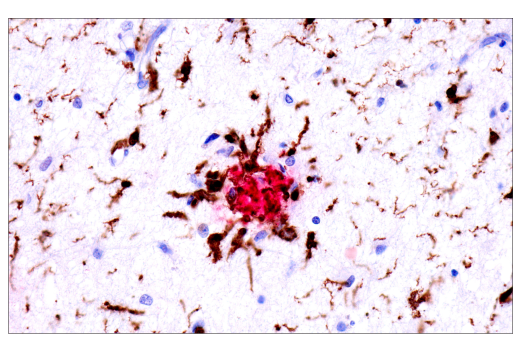

Dual immunohistochemical analysis of paraffin-embedded human Alzheimer's brain using APP/β-Amyloid (NAB228) Mouse mAb (red) and Iba1/AIF-1 (E4O4W) XP® Rabbit mAb #17198 (brown).